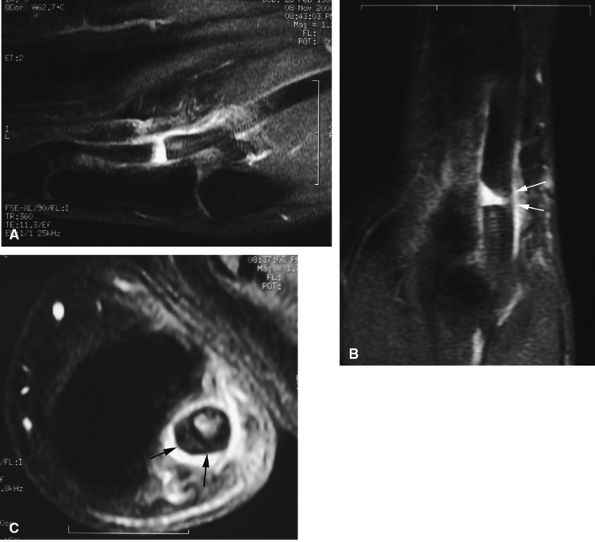

FIGURE 11.47 ● Jersey finger. (A) Sagittal T2-weighted image. (B) Coronal post-contrast T1-weighted images. (C) Axial T1-weighted image. Distal avulsion of the FDP tendon is shown with the proximal end (white arrows) at the metacarpophalangeal joint (type I). The tendon is wavy in the palm (arrowheads). The empty digital canal (in C) may mimic a remnant tendon, but the FDS tendon (asterisk) is alone in the canal.